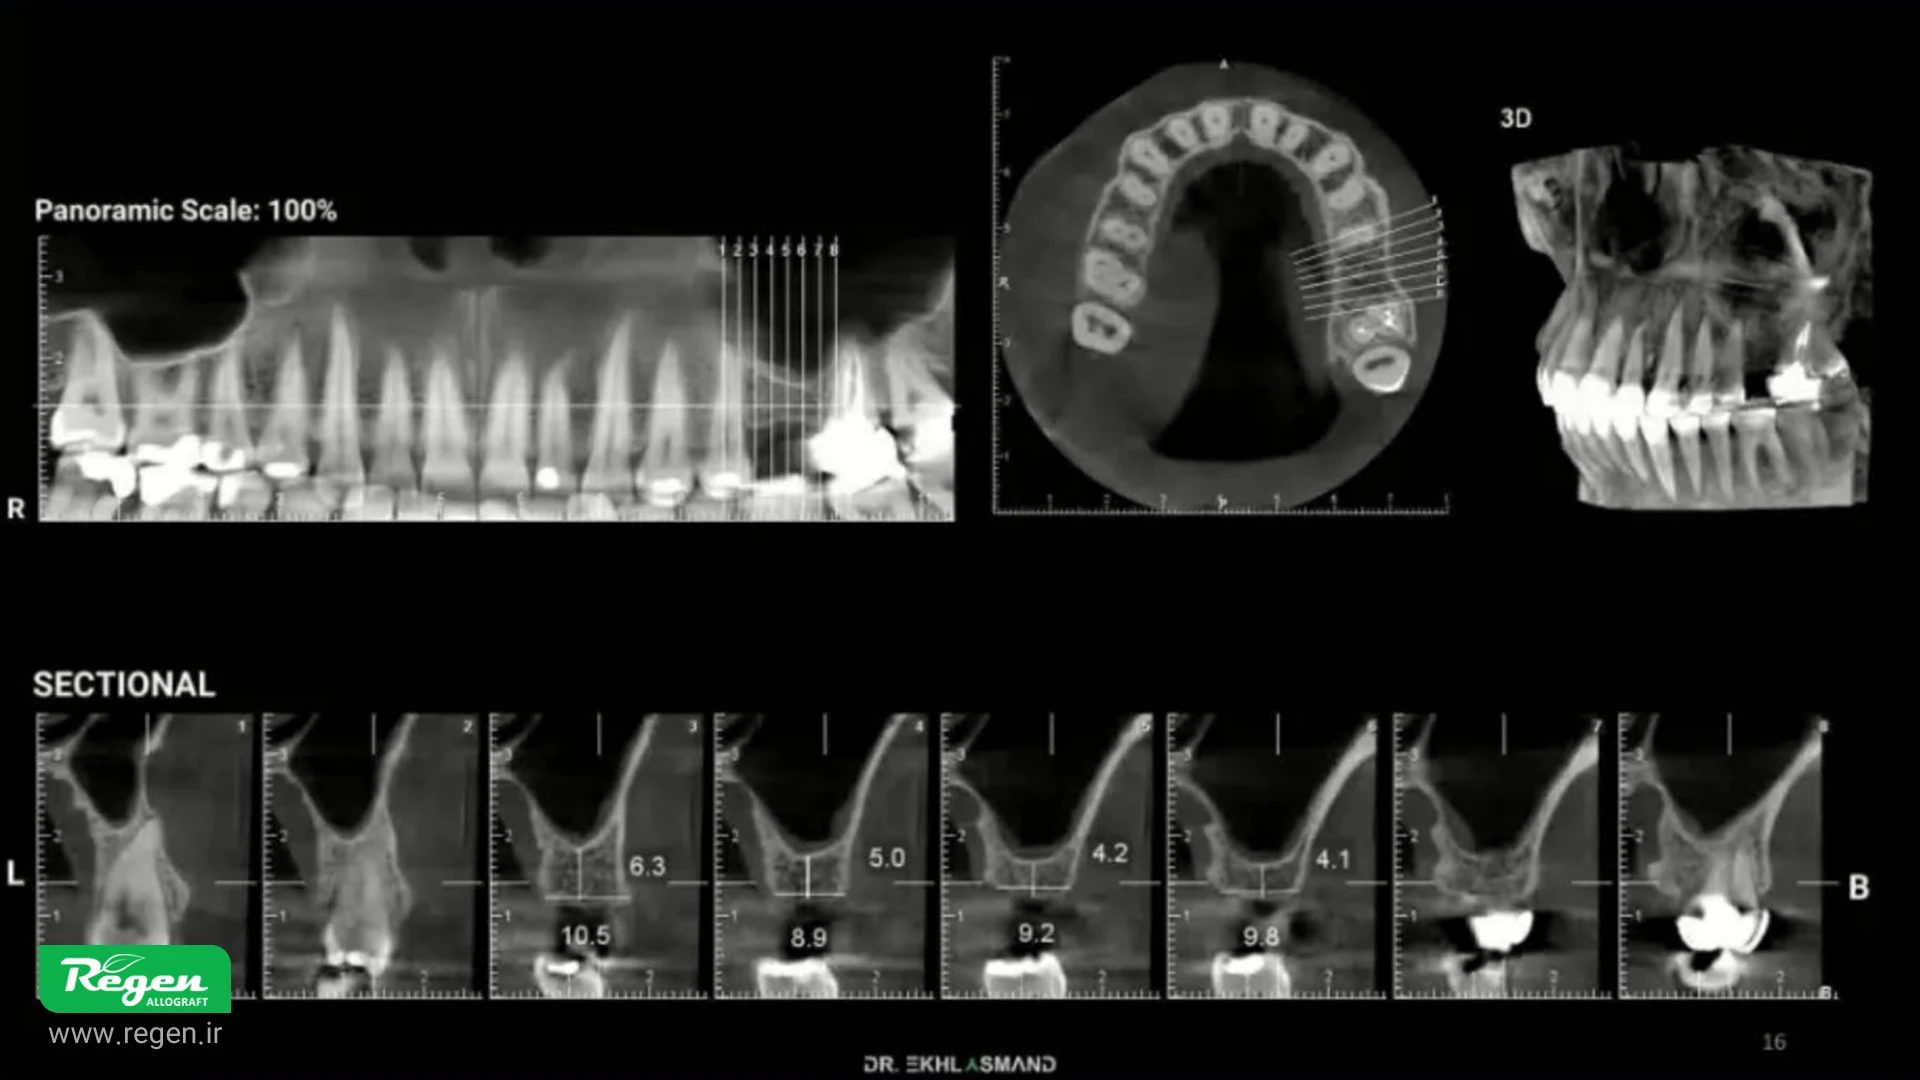

پیش از هرگونه مداخله جراحی، ارزیابی کامل سینوس ماگزیلاری با استفاده از CBCT الزامی است. بررسی تصویر سینوس پنوماتیزه شده با وضوح خوب، شرایط ایدهآل برای شروع کار را فراهم میکند. ضخامت مخاط سینوس (تیکنینگ) در محدوده 0.8 تا 2-2.5 میلیمتر میتواند مفید باشد، زیرا احتمال پارگی غشا (پرفوریشن) را کاهش میدهد.

به طور خلاصه باید که گفت موارد زیر باید در بررسی اولیه مورد توجه قرار گیرند: • شدت پنوماتیزه بودن سینوس • ضخامت غشای اشنایدری (در محدوده ۰.۸ تا ۲.۵ میلیمتر) • وجود یا عدم وجود موکوزیت و التهاب "افزایش ضخامت غشای سینوس میتواند مزیتی در کاهش احتمال پرفوریشن باشد"